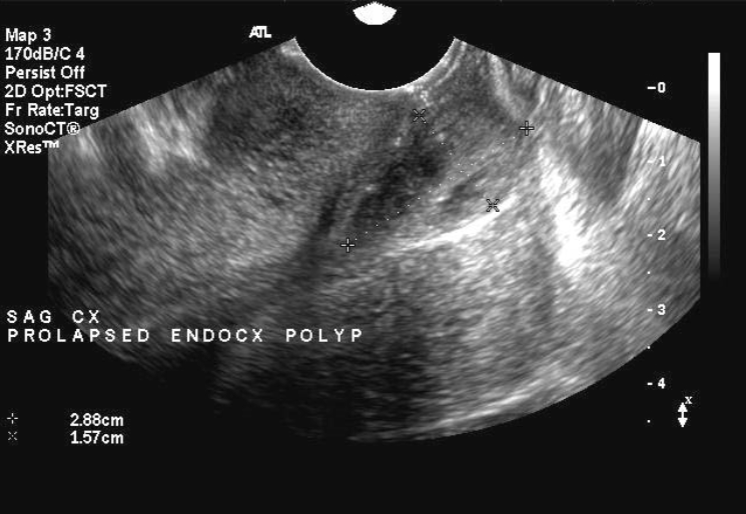

Cervical Polyp

Most common benign cervical lesion

Most often occur in multigravitas, peri or post-menopausal patients

usually asymptomatic

Cervical polyps U/S appearance:

Attached by a stalk to cervical wall

May be difficult to see on US due to size

“teardrop” appearance